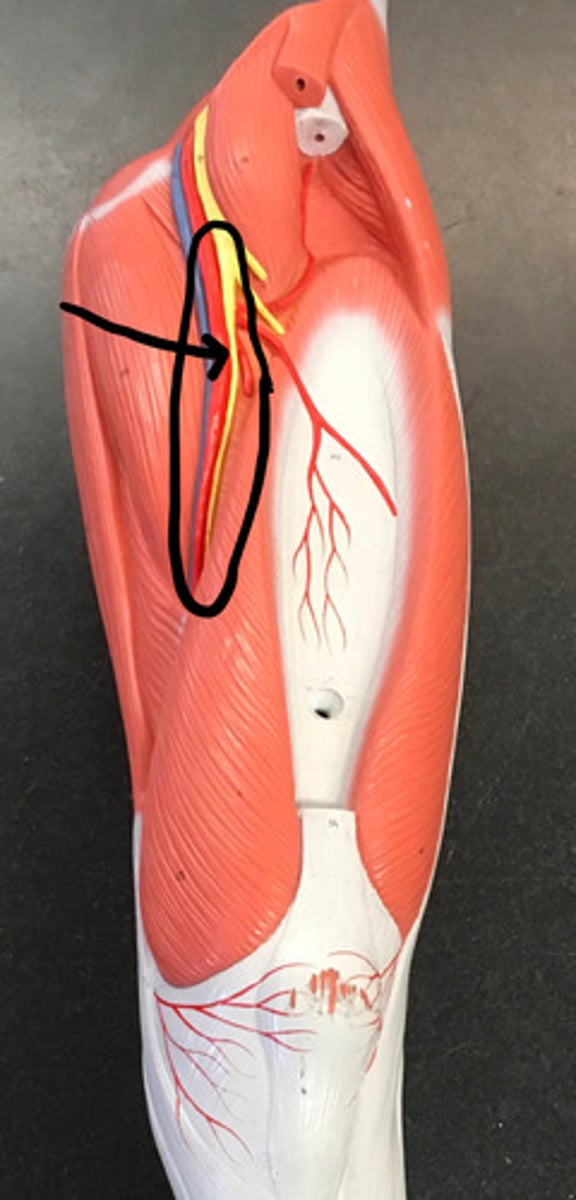

brachial plexus

C5-T1

superior trunk

yellow

middle trunk

orange

inferior trunk

red

lateral cord

pink

medial cord

purple

posterior cord

blue

musculocutaneous nerve

median nerve

ulnar nerve

axillary nerve

dives deep near teres major

radial nerve